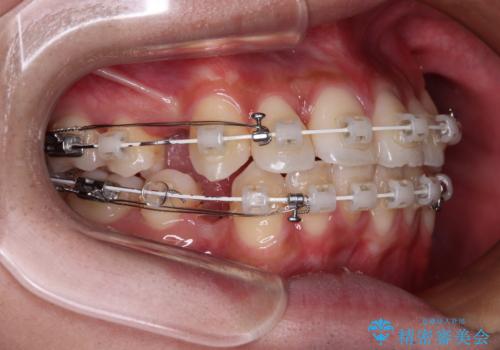

- 矯正装置

- 審美装置

- 2年2ヶ月

- 八重歯と口元の閉じにくさを気にして来院された患者様です。

非抜歯矯正で歯列を整えると、治療後に口元が今よりも突出する可能性が高かったため、上下左右の第一小臼歯4本を抜歯し、ワイヤー装置にて矯正治療を行うこととしました。